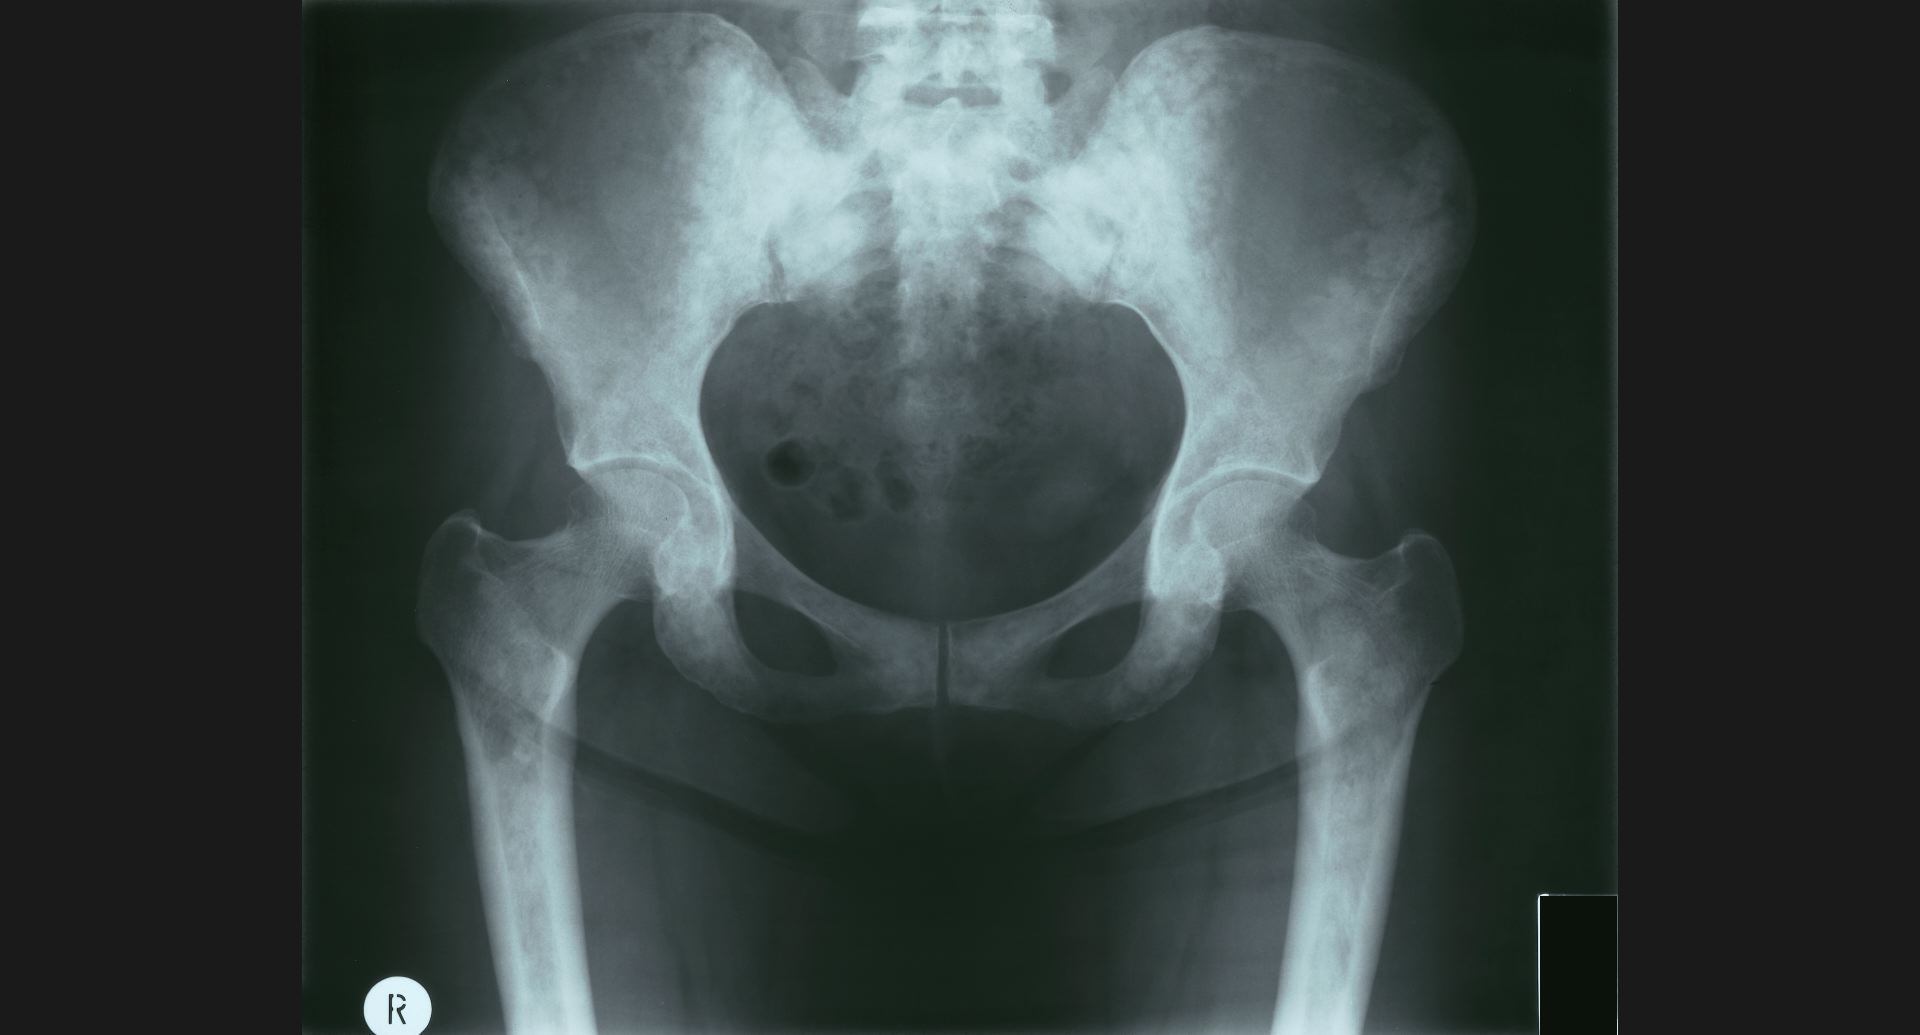

fig.16(93KB)

:Osteoblastic metastases (骨盤)